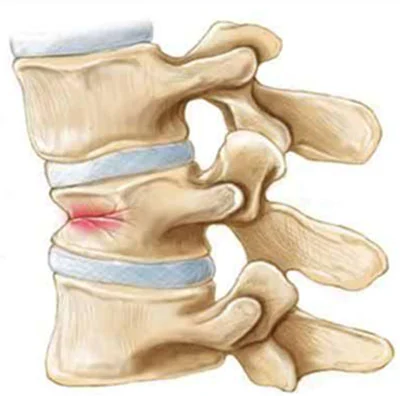

La frattura vertebrale da compressione è una delle forme più comuni di frattura patologica, che si verifica quando la vertebra perde la sua normale densità ossea e si frantuma sotto il peso o la pressione. In molti casi, le fratture vertebrali da compressione si verificano in pazienti con osteoporosi, una condizione che indebolisce le ossa e le rende più fragili. Inoltre, le fratture vertebrali sono frequentemente associate a tumori che colpiscono la colonna vertebrale, come i tumori maligni primari o le metastasi ossee provenienti da altre parti del corpo.

Le fratture vertebrali, se non trattate correttamente, possono portare a gravi complicazioni come dolore cronico, perdita di mobilità, e in alcuni casi, danni permanenti ai nervi. È quindi fondamentale un intervento tempestivo e mirato per ridurre il dolore e favorire la guarigione. I trattamenti per le fratture vertebrali possono includere radiologia interventistica, tecniche minimamente invasive come la vertebroplastica o la kyphoplastica, che permettono di ripristinare la stabilità della vertebra senza ricorrere a interventi chirurgici tradizionali. Queste tecniche vengono eseguite sotto guida radiologica, garantendo alta precisione e riducendo i rischi per il paziente.